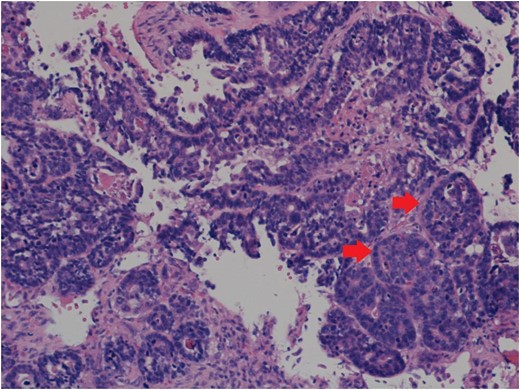

Histology showing paraspinal tissue replaced and permeated by metastatic adenocarcinoma with large areas of necrosis. Arrows point to clusters of tumour cells. Source: Salford Royal Hospital Histology Department.

Histology showed a high grade adenocarcinoma with appearances unlikely to represent a primary adnexal carcinoma. The immunoprofile of the specimen suggested a metastatic deposit of a tumour originating in the gastrointestinal tract or pancreatico-biliary system. In light of this, a CT abdomen, thorax and pelvis was undertaken whilst a referral was made to a gastrointestinal surgeon. CT showed a large tumour of the lower oesophagus with multiple metastatic lymph nodes, bony metastasis in vertebrae L2 and lung metastases. Oesophageal biopsies confirmed an invasive adenocarcinoma, just superior to the gastro-oesophageal junction. Spinal decompression and stabilization was undertaken, in order to maintain quality of life, and he was discussed at the UGI MDT where it was decided that treatment would be palliative in nature. Radiotherapy involved five fractions to the lumbar spine and right cheek, before referral to a medical oncologist for palliative chemotherapy. The cheek mass had responded well to radiotherapy and the patient was placed on a course of epirubicin, oxaliplatin and capecitabine (Xeloda, Manufacturer Hoffman La Roche) for the oesophageal tumour. On review, a CT scan showed progression of bony disease and lung metastases along with a collapse of C4, and at this point the oncologist estimated survival to be that of 3–6 months. The patient died soon after.